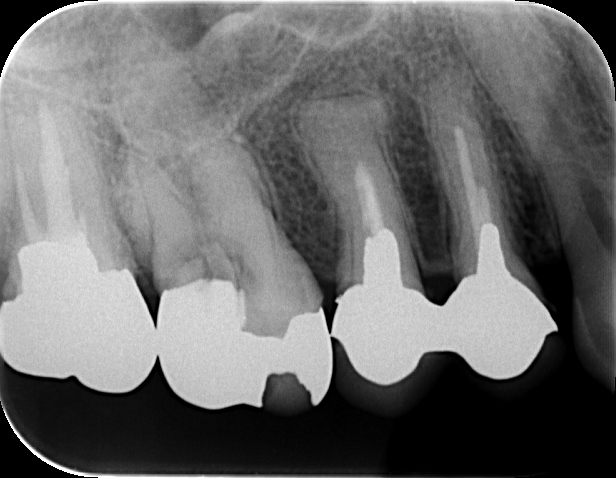

抜髄後、根管内を適切に処置し、最終的にコア(土台)→被せ物まで進めました。

術後4年

抜髄後は痛みが軽減し、その後の経過も良好でした。